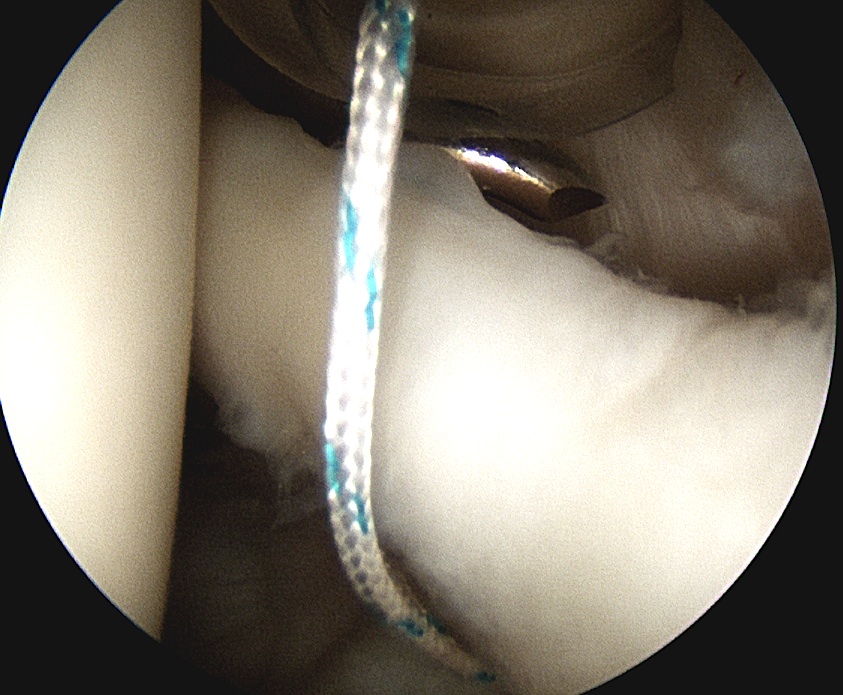

3. Anchors

Drill and insert via Wilminton portal

- insert anchor

- suture through each cannula

- limb through W portal will be the suture limb that is passed

- suture passer through anterior portal (right angled for left shoulder)